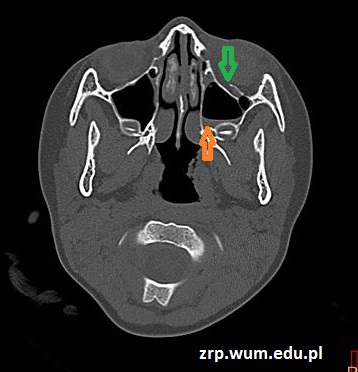

Przypadek 47: 5-letnia dziewczynka po urazie okolicy oczodołu lewego, obrzęk okolicy policzka lewego. Bez utraty przytomności, bez wymiotów. Podsypiająca.

Rozpoznanie: W badaniu TK stwierdzono złamanie dolnej ściany oczodołu lewego (zielona strzałka) z płynem w lewej zatoce szczękowej (pomarańczowa strzałka).